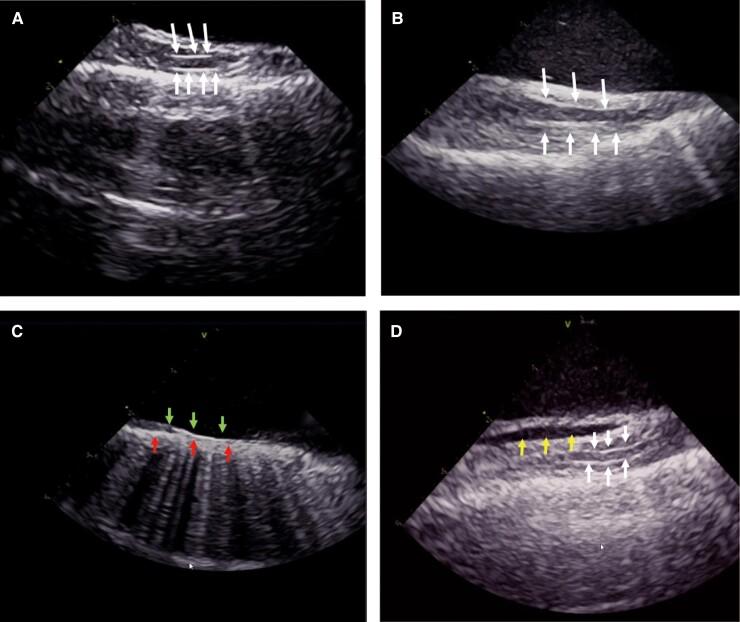

The RPN was detected using ICE. The RPN and its adjacent structures were analysed. The relationship between the RPN's distance from the superior vena cava (SVC) and its pacing capture threshold was quantified. The safety of SVC isolation guided by the ICE-visualized RPN was evaluated. Thirty-eight people were enrolled in this study. The RPN was visualized by ICE in 92% of patients. It ran through the space between the SVC and the mediastinal pleura and had a 'straw'-like appearance upon ICE imaging. The course of the RPN was close to the SVC (minimum 1.0 ± 0.4 mm) and the right superior pulmonary vein (minimum 14.1 ± 7.3 mm). There was a positive linear correlation between the RPN's capture threshold and its distance from the SVC (Spearman's correlation coefficient = 0.728, < 0.001). SVC isolation was guided by the RPN; none of the patients developed an RPN injury.